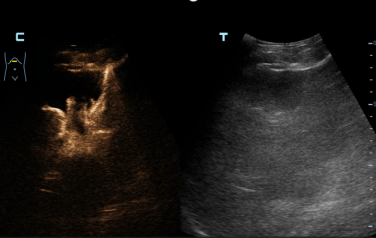

术前面临的主要挑战在于患者左肝胆管位置较高、走行迂曲,可供安全穿刺的窗口极为有限。该院超声科主治医师李西接手后,在超声影像的清晰引导下,对穿刺路径进行了毫米级的精细规划。术中,在超声「导航」下,李西医师手法娴熟,穿刺针在手中游刃有余,精准地避开血管,直抵目标胆管,随即墨绿色的胆汁从针芯流出—「一针」成功!随后,在助手的配合下,李西依次置入导丝和导管。术后即刻行超声造影显示双侧肝内胆管显影,引流管位置理想,胆汁引流通畅。术后患者生命体征平稳,黄疸症状明显缓解。为表达对超声介入团队的高度认可和衷心感谢,患者家属专程送来了锦旗。